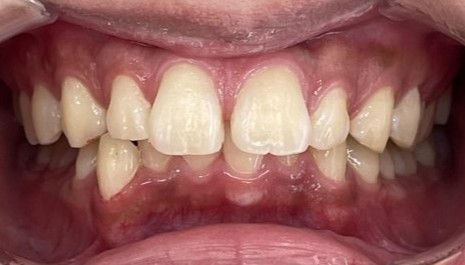

Before

After

矯正の種類 / invisalign GO

年齢・性別 / 10代女性

主訴  /  上下顎叢生

治療期間 / 15ヶ月

費用 / 簡易検査 5,000円(税別) 精密検査 30,000円(税別)

両顎マウスピース 450,000円(税別) 両顎リテイナー料 40,000円(税別)

※マウスピース交換時別途調節料5,000円(税別)

副作用 / 口内炎・歯の移動に伴う痛み・知覚過敏 ※数日で収まる場合が多いです

リスク / 後戻り防止の為、夜のみマウスピースで保定を指示